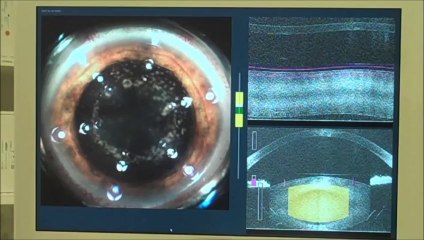

Cataract Surgery By Private Practice of Mr Mahi Muqit PhD FRCOphth

Mr Mahi Muqit PhD FRCOphth is a Consultant Ophthalmologist, Cataract and Vitreoretinal Surgeon at the world famous Moorfields Eye Hospital in London. He runs a private practice at both Moorfields Private and at 119 Harley Street in London.